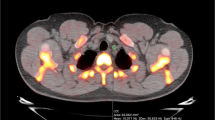

SUV was calculated using the operator-guided computer software PMOD (PMOD

Technologies LLC, Switzerland). CT and PET images for each participant were uploaded onto the software and manipulated to create regions of interest (ROIs) on each CT image slice. This was done by segmenting regions around the heart on each 3.75-mm thick coronal slice, moving anteriorly to posteriorly. These ROIs were then stacked to create 3D volumes of interest (VOIs). The VOIs encompassed only the vascular tissue of the heart—blood and the surrounding thoracic cavity were excluded by setting a threshold with a lower limit of – 50 HU (Fig. 1). The VOIs were generated using the CT images for structural clarity, then superimposed on the corresponding PET images. From here, average SUV (SUVmean) and maximum SUV (SUVmax) were calculated within each VOI.

Comparing patients to controls

Despite having similar HU values (0.88 HU lower among patients, CI − 3.05–1.30, P = 0.42), compared to matched controls, patients had higher SUVmean (0.09 g/mL higher among patients, CI 0.03—0.15, P = 0.01), but not SUVmax (0.04 g/mL lower among patients, CI − 1.06–0.98, P = 0.94; Fig. 2), which was quite noticeable visually (Fig. 3). Patients also had higher 10-year Framingham Risk Scores (2.45 higher among patients, CI 0.46–4.45, P = 0.02; Fig. 4). However, no differences were detected between patients and healthy controls on any calcium score measure (calcium mass, 58 mg lower among patients; CI − 481.93–365.93, P = 0.75; calcium volume, 65.71 mm lower among patients; CI − 458.34–326.91, P = 0.70; calcium score, 69 AU lower among patients; CI − 622.25–484.25, P = 0.77; Fig. 5).

Many of the procedures that diagnose and monitor coronary plaque deposition are invasive and are often limited to acute coronary events [1, 18, 20]. Coronary computed tomography angiography (CCTA), X-ray angiography, and intravascular ultrasound monitor the amount of calcification in the vessels, and are therefore often a better assessment of disease burden than of near coronary event risk [18]. Arterial stenosis does not correlate with risk of an event. Single-photon emission computed tomography (SPECT) is a functional assessment to determine how the heart responds with added stressors, often exercise or an adenosine injection to mimic exercise’s effects. No quantification of plaque in the arteries results from this method. The benefits of 18F-NaF PET/CT imaging in the context of current available imaging modalities is that it provides a way for clinicians to quantify subtle changes in plaque deposition that are not visible to the human eye (picomolar tissue concentrations). Early vascular calcification (microcalcification) in response to inflammation can be detected by NaF below CT resolution [26,27,28,29,30,31]. It is a method that is less invasive than angiography. NaF PET/CT imaging utilizes a biochemical method and offers quantitative measurement of calcified plaque in the coronary arteries [10,11,12, 17, 32,33,34]. This method bypasses the need for subjective recognition with the naked eye by a radiologist, which may explain why calcium scores did not differ between patients and controls [12, 17]. Our methodology for calculating SUV only relied on the eyes of the technician for gross anatomic identification. A preliminary circle was drawn around the heart with the only requirement being that no outside bone or soft tissue be present in the VOI. Then, the VOI was automatically segmented using PMOD software to include HU values that were above a specific threshold of – 50 HU. Even computer-derived CT values obtained from this segmentation did not differ between patients and controls or correlate with age or BMI. This suggests that NaF’s utilization of a functional pathway renders it sensitive to the formation of microcalcification long before it becomes detectable calcification.